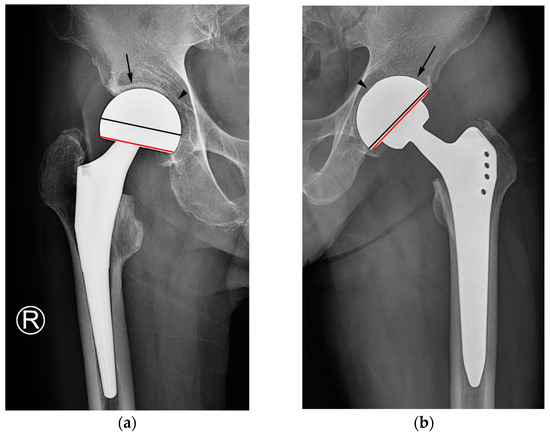

Figure 4.

Simple radiographs of hemiarthroplasty (a) and THA (b). In bipolar hemiarthroplasty (a), the subchondral bone plate of the acetabulum and the adjacent joint space (arrow) are preserved, and the outer surface of the cup appears smooth instead of rough (arrowhead). The chord line of the cup (red line) deviates from the sphere’s equator. In THA (b), the subchondral bone endplate and cartilage space are absent (arrow), and the interface between the cup and bone is smooth, displaying a subtle indentation of the outer spherical contour (arrowhead). The chord line of the cup (red line) closely approaches the equator of the sphere (black line). In both images, the black line represents the equator of the sphere, whereas the red line indicates a chord line connecting the medial and lateral edges of the acetabular cup or bipolar head.